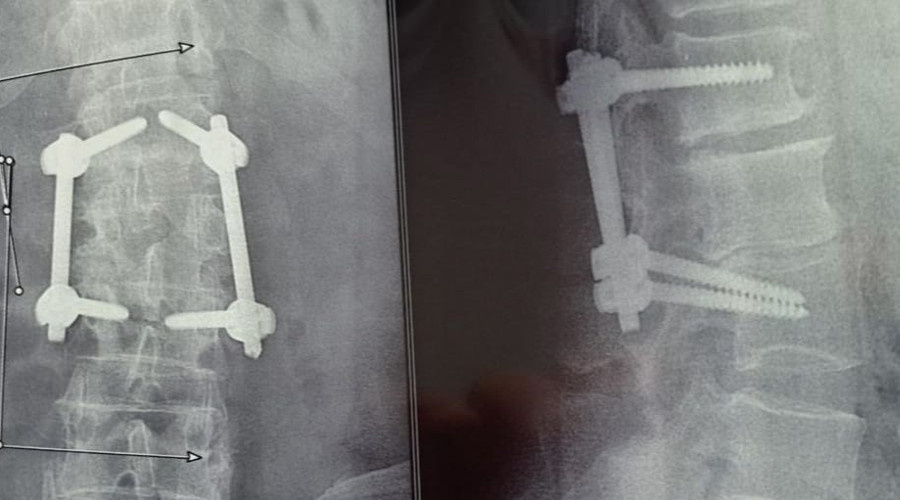

Как сообщает Балаковская городская клиническая больница, в минувшую субботу, 18 января, нейрохирург Балаковской городской клинической больницы Александр Юрьевич Майоров был приглашен представителями известного Екатеринбургского завода, специализирующегося на производстве инструментов и оборудования медицинского назначения, в том числе для нейрохирургии позвоночника, в одну из клиник города Энгельса для проведения демонстрационной операции на позвоночнике по стабилизации поясничного отдела со специальными приспособлениями, изготовленными с использованием титана, который не вызывает аллергию и не отторгается организмом.

Нейрохирургом Александр Майоровым была проведена транспедикулярная 4-ех винтовая фиксация 1 и 3 позвонков, ввиду нестабильности двух сегментов поясничного отдела позвоночника и вторичного воспаления 2-го поясничного позвонка. Операция прошла успешно. И теперь пациент постепенной пойдет на поправку.